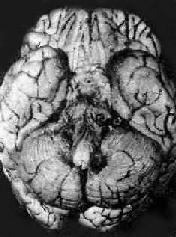

图18-13 结核性腹膜炎 腹膜上满布无数结核结节 2.干型其特点为腹膜上除见结核结节外尚有大量纤维素性渗出物,机化后引起腹腔器官,特别是肠管间、大网膜、肠系膜广泛紧密粘连。大网膜一般增厚、变硬和缩短。肠系膜也显著缩短。坏死严重者可在粘连的肠管之间或向腹外溃破形成瘘管。病人因肠粘连而出现慢性肠梗阻症状。腹上部可扪得一横行块状物,为收缩粘连的大网膜。并因腹膜增厚触诊时有柔韧感或橡皮样抗力。 (三)结核性脑膜炎 结核性脑膜炎以小儿多见,成人较少。主要由于结核杆菌经血道播散所致。在小儿往往是肺原发综合征血行播散的结果,故常为全身粟粒性结核病的一部分;在成人除肺结核病外,骨关节结核和泌尿生殖道结核病常是血源播散的根源。部分病例也可由于脑实质内的结核球液化溃破,大量结核菌进入蛛网膜下腔所致。 病理变化以脑底最明显。在脑桥、脚间池、视神经交叉及大脑外侧裂等处之蛛网膜下腔内,有多量灰黄色混浊胶冻样渗出物积聚。偶见比粟粒还小的灰白色结核结节(图18-14)。脑室脉络丛及室管膜有时也可有结核结节形成。镜下,蛛网膜下腔内炎性渗出物主要由浆液、纤维素、巨噬细胞、淋巴细胞组成,常有干酪样坏死,偶见典型结核结节形成。病变严重者可累及脑皮质而引起脑膜脑炎。病程较长则可发生闭塞性血管内膜炎,从而可引起多发性脑软化。未经适当治疗致病程迁延的病例,由于蛛网膜下腔渗出物的机化而发生蛛网膜粘连,可使第四脑室上中孔和外侧孔堵塞,引起脑积水。

图18-14 结核性脑膜炎 脑基底部脑膜增厚,有散在的结核结节 (四)泌尿生殖系统结核病 1.肾结核病 最常见于20~40岁。男性多于女性。多为单侧性、双侧性肾结核的发病率约为10%。病变开始于肾皮、髓质交界处或乳头体内。初为局灶性结核病变,病变继续扩大发展则发生干酪样坏死,破坏肾乳头而溃破入肾盂,成为结核性空洞。随着病变在肾内扩大蔓延,形成多数结核空洞,最后可使肾仅剩一空壳(图18-15)。由于液化的干酪样坏死物可随尿液下行,常使输尿管及膀胱感染。输尿管粘膜可发生溃疡和结核性肉芽组织形成,使管壁增厚、管腔狭窄,甚至阻塞,结果常引起肾盂积水或积脓。膀胱三角区往往最先受累,形成溃疡,以后可侵及整个膀胱,可引起膀胱壁纤维化,使膀胱容积缩小(膀胱挛缩)。膀胱的溃疡和纤维组织增生如影响到对侧的输尿管口,可使管口狭窄或失去正常的括约肌功能(关闭不全),造成对侧健肾引流不畅,最终可引起肾盂积水。结核菌也可逆行感染对侧肾。